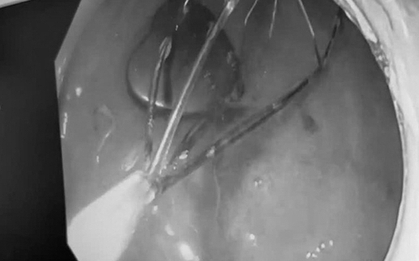

Bé gái 3 tuổi bị sốt cao, ho nhiều, được chẩn đoán viêm phổi và nằm viện gần 30 ngày nhưng tình trạng không thuyên giảm. Trong quá trình siêu âm, bác sĩ phát hiện ổ bụng trẻ có khối lạ nghi dị vật, lập tức chuyển bệnh nhi đến Bệnh viện Nhi đồng 2.